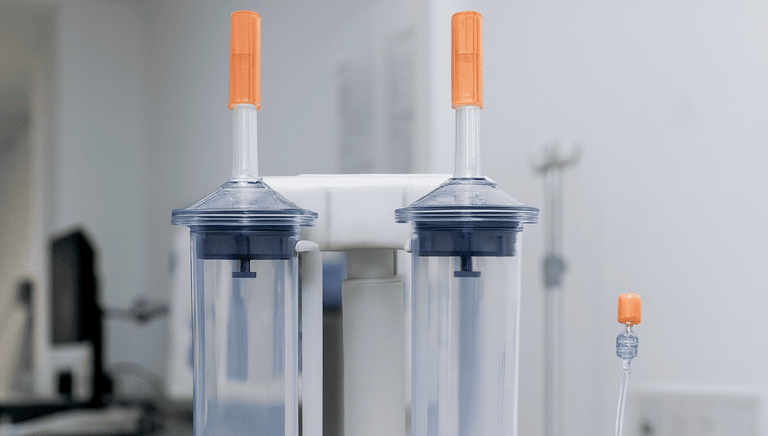

Inyector automatizado que administra medios de contraste en estudios de tomografía computarizada (TC).

Jeringa estéril diseñada para inyectores automáticos de medios de contraste en estudios de imagenología